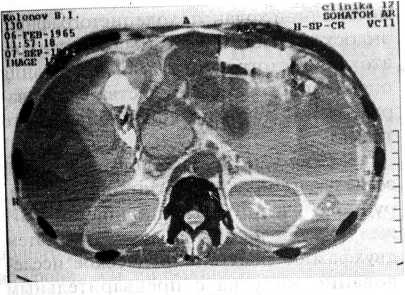

Хронический панкреатит (50 набл.) характеризовался увеличением размеров различных отделов железы, неоднородностью структуры, наличием истинных и ложных кист, исчезновением границ между железой и окружающими тканями, дуоденостазом и гастроптозом (рис. 1).

Рис. 1. Киста головки поджелудочной железы, сдавливающая просвет двенадцатиперстной кишки и терминального отдела холедоха у больного С., 37 лет. Кистозный панкреатит, подтвержденный в ходе операции.